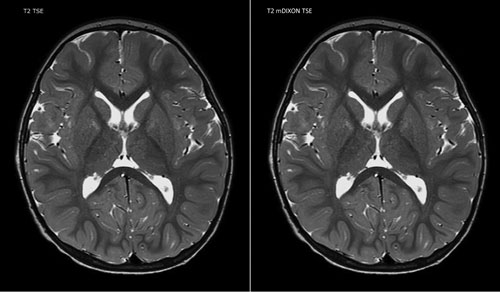

Crozer Health is Delaware County's leading choice for comprehensive outpatient medical imaging services Our goal is to provide patients with a quality experience from start to finish at each of our imaging centers Most services have appointments available within 24 hours, and reports are available to referring physicians. The Medical Imaging Informatics market report can be customized according to the need of the clients This means that the DataIntelo can provide a complete analysis of that one particular product. MRI Transcription Sample Reports For Medical Transcriptionists MRI Transcription Sample Report #1 MRI SCAN OF THE BRAIN WITH AND WITHOUT CONTRAST DATE OF STUDY MM/DD/YYYY CLINICAL HISTORY Focal speech deficits Multiplanar sagittal, axial and coronal images were obtained through the brain prior to and following contrast administration.

MRI OF THE BRAIN WITH AND WITHOUT CONTRAST TECHNIQUE MRI was performed of the brain prior to and following the administration of IV gadolinium utilizing standard protocol No prior study is available for comparison CLINICAL INFORMATION The basilar cisterns, ventricular system and cortical sulci appear unremarkable for a 67yearold patient The visualized mastoid air cells and paranasal. * US Patent Pending 61/551,473 "Method and apparatus for providing radiological second opinion”;. All told, medical data from more than 16 million scans worldwide was available online, including names, birthdates and, in some cases, Social Security numbers Experts say it’s hard to pinpoint.

Your doctor sometimes uses medical imaging to diagnose and treat diseases they think you may have A radiologist is a doctor who supervises these exams, reads and interprets the images, and writes a report for your doctor This report may contain complex words and information. MRI OF THE BRAIN WITH AND WITHOUT CONTRAST TECHNIQUE MRI was performed of the brain prior to and following the administration of IV gadolinium utilizing standard protocol No prior study is available for comparison CLINICAL INFORMATION The basilar cisterns, ventricular system and cortical sulci appear unremarkable for a 67yearold patient The visualized mastoid air cells and paranasal. SCAN Health Plan is an HMO plan with a Medicare contract Enrollment in SCAN Health Plan depends on contract renewal SCAN also contracts with the California Department of Health Care Services for Medicare/MediCal eligible beneficiaries.